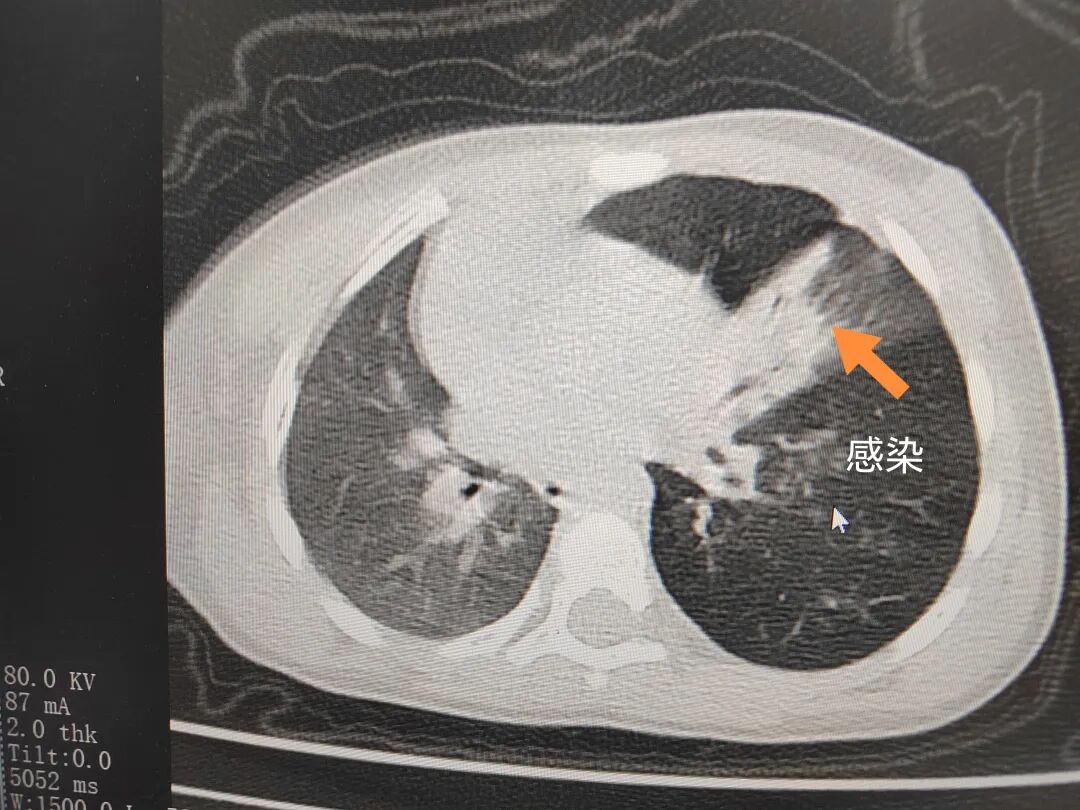

三天后(11月13日),趙寶出現(xiàn)高熱、咳喘加重,家長(zhǎng)著急了,再次帶他來(lái)到醫(yī)院。CT檢查顯示左肺過(guò)度充氣,左肺上下葉支氣管主干見(jiàn)不規(guī)則高密度影,左肺上葉可見(jiàn)大片狀密度增高影,縱隔窗實(shí)變,提示為“左側(cè)支氣管內(nèi)異物并繼發(fā)性改變,左肺上葉舌段肺膨脹不全”。

市二院小兒呼吸內(nèi)科團(tuán)隊(duì)迅速為患兒制定了周密的手術(shù)方案,并很快安排了氣管鏡探查。術(shù)中,主治醫(yī)師田慧等憑借嫻熟的氣管鏡操作技術(shù)成功將異物大塊板栗取出。由于板栗在氣管內(nèi)存留時(shí)間較長(zhǎng),質(zhì)地軟糯易碎,大大增加了手術(shù)難度。檢查還發(fā)現(xiàn),異物停留部位的氣管黏膜已出現(xiàn)充血紅腫、糜爛,導(dǎo)致患兒住院時(shí)間相應(yīng)延長(zhǎng)。此次事件給趙寶的家庭帶來(lái)了不小的驚嚇與擔(dān)憂,也再次為廣大家長(zhǎng)敲響了警鐘。

市二院小兒呼吸內(nèi)科副主任楊亞娟介紹,異物誤入氣道可能導(dǎo)致氣道阻塞,嚴(yán)重時(shí)可引發(fā)窒息,甚至危及生命。若異物進(jìn)入支氣管,造成不完全堵塞,可引起阻塞性肺氣腫;如完全堵塞支氣管,則可能導(dǎo)致肺組織萎縮,形成肺不張。此外,若異物存留時(shí)間較長(zhǎng),或?yàn)橹参镄援愇铮菀缀喜⒓?xì)菌感染,產(chǎn)生膿性分泌物,進(jìn)而發(fā)展為肺炎。她強(qiáng)調(diào),盡早診斷并取出異物,是減少并發(fā)癥、降低病死率的關(guān)鍵。